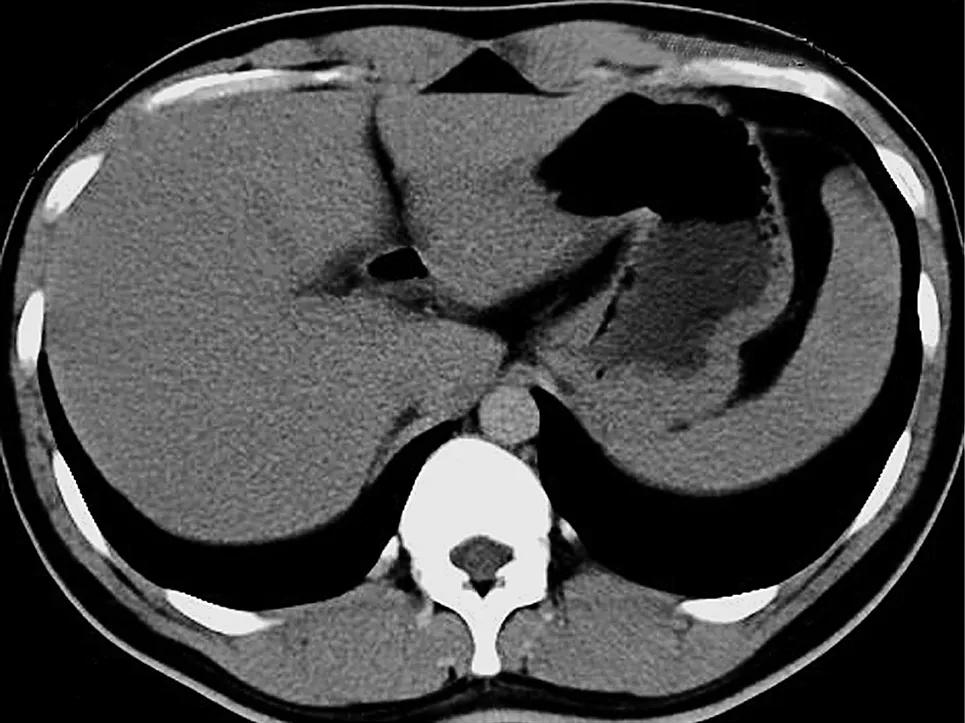

肝脏CT检查是目前临床上常用的肝脏影像学检查方法之一。它通过计算机断层扫描技术,利用X射线对人体进行断层扫描,并通过计算机重建图像,从而显示肝脏的内部结构和病变情况。

肝脏CT检查具有较高的分辨率,能够检出直径1.0cm左右的微小癌灶。特别是在诊断肝硬化、肝癌等疾病时,CT检查具有明显的优势。研究表明,肝脏CT检查对于肝硬化的确诊准确率高达80%,并且可以判断肝硬化是否有癌变的可能。此外,CT检查还可以显示肝内占位性病变、原发和转移性肿瘤的形态、轮廓、坏死、出血、钙化、血供情况以及生长方式等信息。